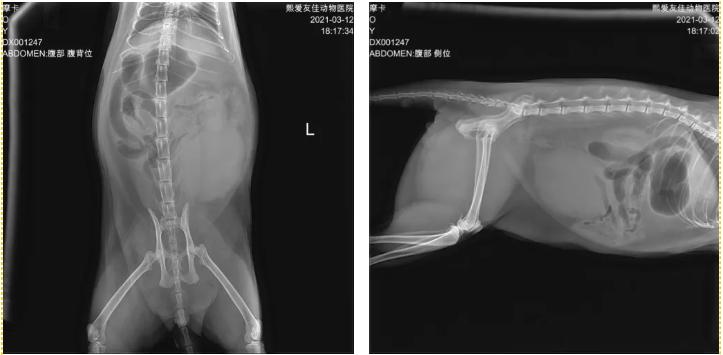

视诊:患猫倒地不起,牙龈苍白,口腔异味,流涎明显,CRT>2s,脱水程度大于5%。触诊腹部疼痛表现,膀胱过度冲盈。听诊心率90次/min,呈休克状态。

诊断过程:猫咪心率下降,膀胱过度充盈,更多诊断方向考虑下泌尿道堵塞引起的水合代谢异常表现,脱水严重的表现,不排除出现肾衰竭症候群,引起心肾联合疾病综合症。

治疗方法:通过血液学和影像学检查,印证推测,快速建立双静脉通路,及时补充调节离子平衡问题,调节机体酸碱平衡,猫咪心率和机体状态很快得到改善,之后插尿管导尿,缓解猫咪的窘迫症状,猫咪随精神好转可站立行走。